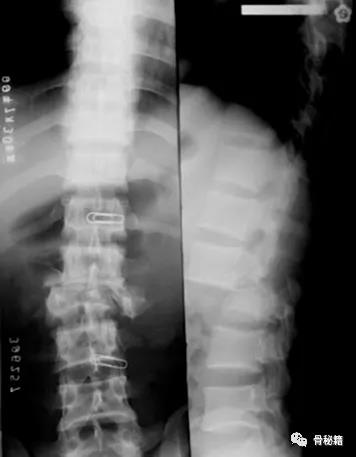

高能量损伤造成的脊柱骨折前后脱位是脊柱骨折复位的难点和要点

前后移位